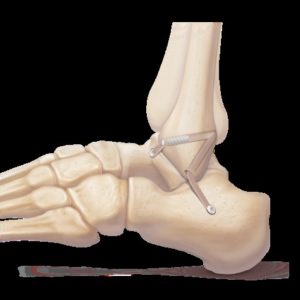

Ankle Ligament Repair For Sprained Unstable Ankles

Picture showing arthroscopic ankle ligament repair

Diagram representing ankle ligament repair